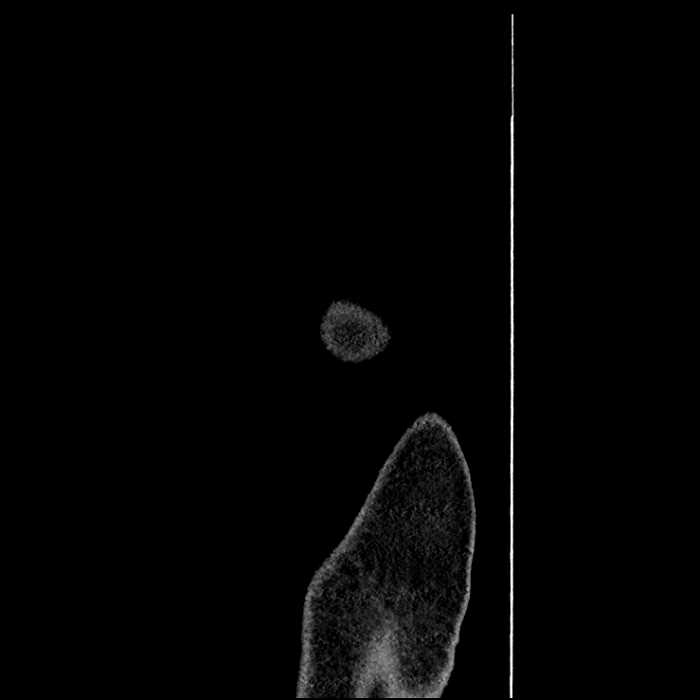

• Incidental splenule